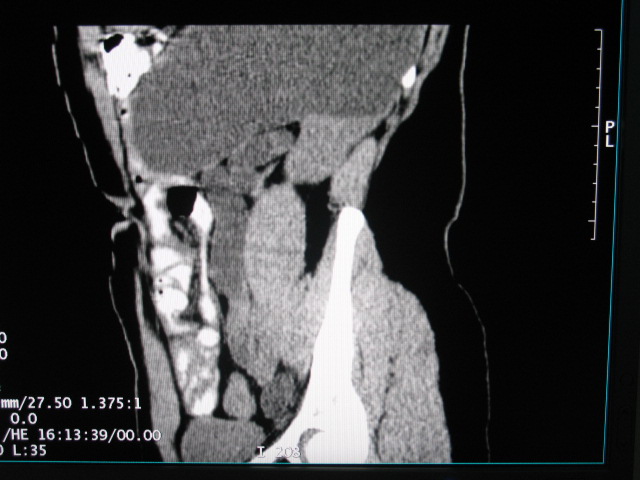

女,28岁,自觉腹部包块一年余

左侧为扩张的输尿管,一直延续到膀胱,那么它的上端应该是扩张的肾盂,但是在他的下方我们看到一个比较正常的肾,所以考虑左侧重复肾盂输尿管畸形。

考虑左侧双肾盂双输尿管畸形,其中一输尿管末端梗阻(不排除异位开口可能)并相应之肾盂及输尿管明显扩张积水。

考虑左侧双肾盂双输尿管畸形,其中一输尿管末端梗阻并输尿管肠管样扩张盂曲、肾盂囊状扩张积水。

左双肾盂输尿管畸形.其一输尿管远端输尿管囊肿引起一肾盂输尿管积水.

考虑左侧双肾盂双输尿管畸形,其中一输尿管末端梗阻(不排除异位开口可能,不知病人有无不自觉溢尿,有可能开口于阴道或宫颈,也可下端为盲端)并相应之肾盂及输尿管明显扩张积水。

术后证实是左侧双肾盂双输尿管畸形,巨输尿管巨肾盂症